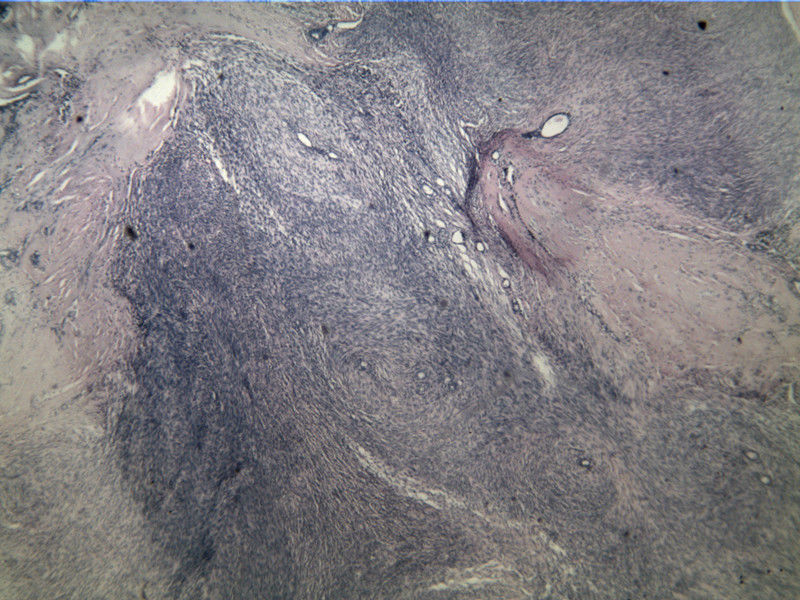

B3817

包块-有包膜(V3x3x2,39y)

图3

叶状肿瘤 导管周间质肿瘤